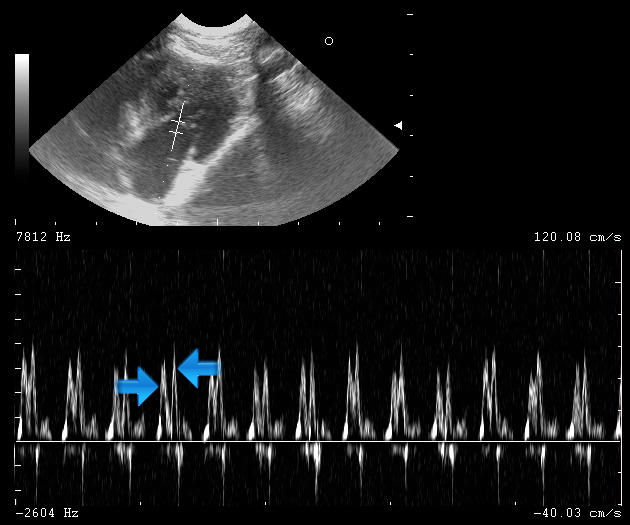

Diagnózu můžeme pak ještě potvrdit pomocí dopplerovského zobrazení průtoku krve mitrální chlopní (z levé síně do levé komory). Krev protéká ze síně do komory ve dvou fázích. Na spektrálním doppleru se tento průtok zobrazuje jako dvě po sobě následující vlny (označené šipkami). První vlna znázorňuje první fázi plnění komory krví, které vzniká roztažením (relaxací) srdečního svalu. Druhá vlna znázorňuje druhou fázi plnění komory, která je způsobená stažením síně. Za normálních okolností je první fáze masivnější a rychlejší, proto se pomocí dopplerovského zobrazení jeví jako vyšší. U hypertrofické kardiomyopatie dochází ke slabší relaxaci komor a tím nižší první vlně.

Echokardiografie-HCM-spektrální dopplerovské zobrazení